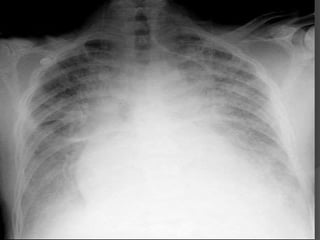

 Chest xray

How to identifyCardiogenic Shock  History  Physical Exam  EKG  Chest xray  Echocardiogram  Swan-Ganz Catheter